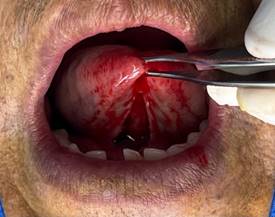

· Desprendimiento nítido del frenillo: Al terminar la primera fase de la diéresis se debe observar el desprendimiento nítido de la inserción del frenillo. Con este desprendimiento se intenta evitar la recidiva. (Figura 5)

Figura 5. Desprendimiento nítido del frenillo.

Elaboración: Los autores.